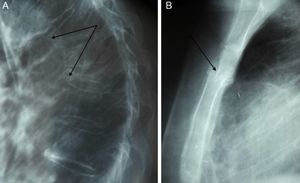

Case ReportA female, 41, attended the emergency department with generalized musculoskeletal pain, especially in the chest, spine and groin. Initial radiographs showed multiple fractures of the upper third of the sternal body, two severe stage 3 dorsal vertebral fractures and a third stages 1–2 dorsal fracture, with another on the ischiopubic ramus (Fig. 1A and B). On examination hypertension and cushingoid features, such as round face and ce obesity were later found. Laboratory studies showed that cortisol and baseline ACTH determination were elevated. The baseline cortisol was 319ng/ml (normal between 50 and 250ng/ml) and ACTH of 57.4pg/ml when it is normally undetectable or less than 10pg/ml, with a decreased gonadotropin level. The levels of urinary free cortisol and cortisol were also elevated at night: 847nmol/l and 290.7ng/ml, respectively. The nocturnal cortisol under normal conditions is negligible. A cranial MRI showed a questionable image in the pituitary, so catheterization of inferior petrosal sinus was performed to study the source of ACTH overproduction. There was a central-peripheral gradient of ACTH and increased focus on the left half of the hypophysis. A second MRI detected a nodule of 6.3mm in the posterior left area of the pituitary. Following these results the patient was diagnosed as having Cushing's disease due to a pituitary microadenoma. The patient was treated from the surgical standpoint with a hemihypophysectomy of the microadenoma, and infused intravenously (iv) with zoledronic acid 5mgiv/year as a treatment for severe osteoporosis, with great improvement of bone pain. After surgery, cortisol levels were normalized with baseline cortisol levels of 152ng/ml and urinary cortisol of 107nmol/l.